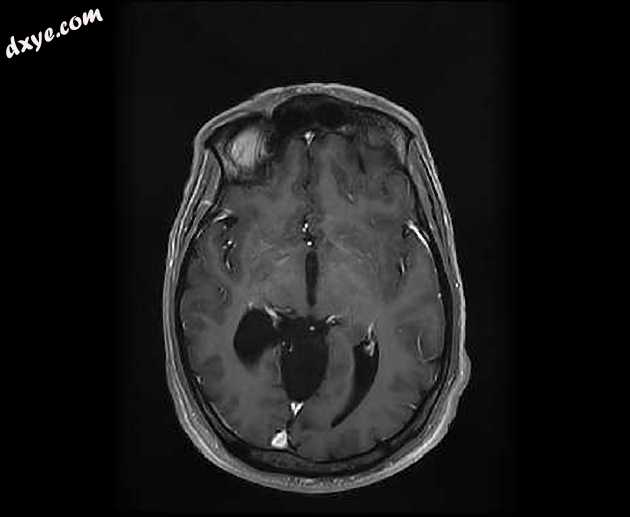

Axial T1 C+

MRI序列显示:

胼胝体弥漫性变薄

侧脑室的平行体

主要在右侧(头畸形)的三角和枕角扩张,在轴向序列上形成“泪珠”构型

小额角

半球间裂增宽

扩张的高位第三脑室

矢状 T1 上脑回的太阳射线外观

扩张的小脑上池

注意右眼假体。